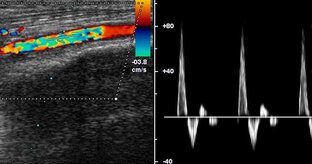

Исследование параметров кровотока геморроидальных артерий с применением высокочастотной ультразвуковой допплерографии

Цель исследования Оценить информативность ультразвукового допплерографического (УЗДГ) исследования геморроидальных артерий (ГА) при геморроидальной болезни (ГБ) II стадии. Материал и методы Проведено УЗДГ ГА 35 пациентам с ГБ II стадии, подтвержденной клинически и эндоскопически на ультразвуковом допплерографе «Минимакс-допплер-К» с использованием 20 МГц эндопросветного датчика с диаметром рабочей части 3 мм. Критерием оценки при УЗДГ ГА являлась максимальная систолическая скорость кровотока (МССК)...